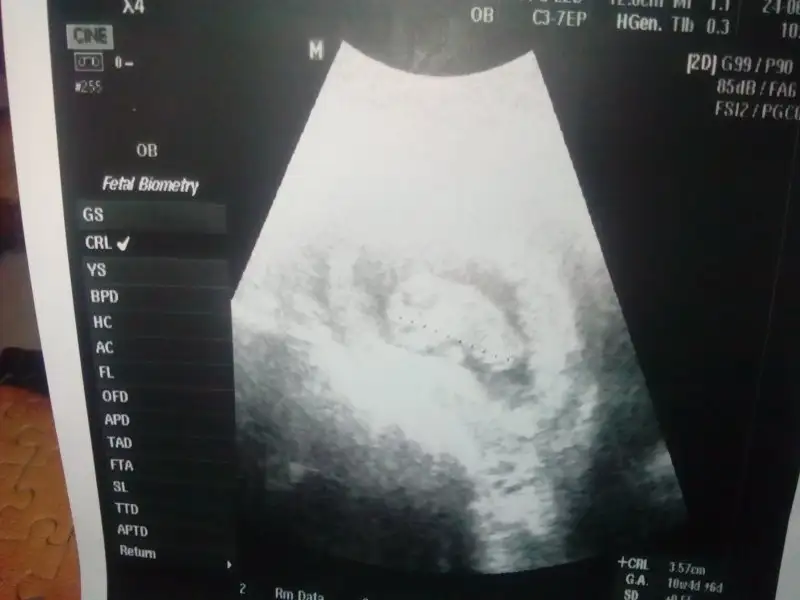

Bugün sudan dolayı kustum biliyor musun.Yemeklerden kusmadım yani ve ilk defa sudan tiksindim. Rapor almak istemiyorum,bayram haftası cuma yokum ve sonraki 3 gün izinliyim fazla göze batarımTamam canim sağol. Su icebiliyor musun ? ben bulanti yüzünden çok az iciyorum. basim agriyor deyince dr suyu fazla tuket demişti tabi ne mümkün su icsem lavaboya koşuyorum. Bu donemde rapor alsan yoğunluk yoksa ? Ben rapor aldim evde yatak yorgan moddayim.